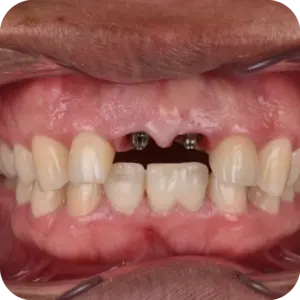

El paciente acudió para rehabilitar las piezas 8 y 9, buscando recuperar funcionalidad y armonía en una zona clave de su sonrisa. Tras la evaluación clínica, se planificó una cirugía guiada y precisa para asegurar estabilidad y proyección estética adecuada.

Se colocaron implantes en ambas piezas con pilares personalizados, logrando una base firme para su futura rehabilitación. El procedimiento fue realizado bajo protocolo quirúrgico controlado, con seguimiento radiográfico posterior.

Hoy cuenta con una solución estable y planificada al detalle, que permitirá devolverle seguridad, funcionalidad y una sonrisa natural.